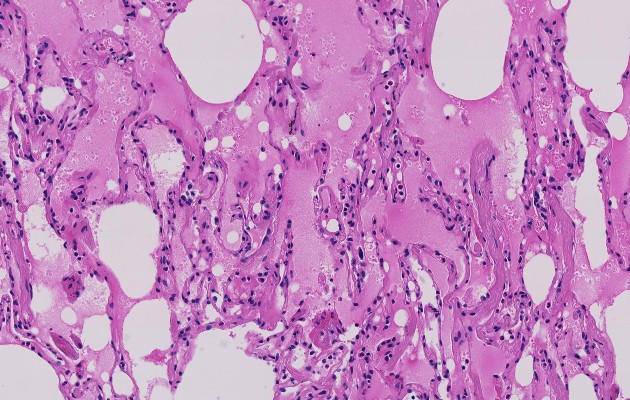

Alveolos pulmonares, llenos de líquido rosa y espeso. Foto / Shu-Yuan Xiao.

El virus luego “avanza progresivamente hacia los bronquios”, explicó Schaffner. Cuando el virus llega a los pulmones, sus membranas mucosas se inflaman. Eso puede dañar los alveolos pulmonares, que tienen que trabajar más para suministrar oxígeno a la sangre y eliminar el dióxido de carbono de la sangre.

La inflamación y el flujo de oxígeno impedido pueden causar que esas áreas en los pulmones se llenen de fluido, pus y células muertas. Puede desarrollarse neumonía, una infección de los pulmones.

Algunas personas batallan tanto para respirar que deben ser conectadas a un ventilador. En los peores casos, conocidos como Síndrome de Dificultad Respiratoria Aguda, los pulmones se llenan de tanto fluido que no hay apoyo respiratorio que sea suficiente y el paciente muere.